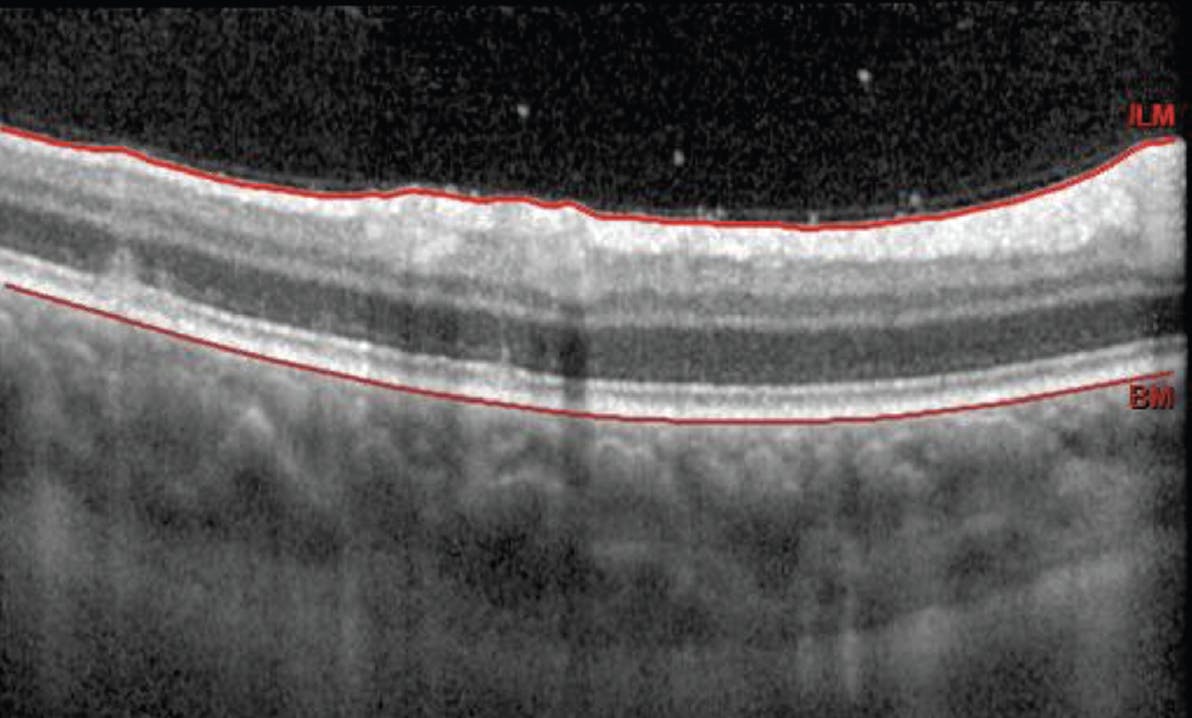

Her BCVA was 20/30-2 OD and 20/20 OS, and she now reported having a floater in her right eye that was blocking her vision. Entrance testing was normal and anterior slit-lamp examination was unremarkable. IOPs via Goldmann applanation tonometry were 14 mm Hg OU. A dilated fundus examination of the patient’s right eye revealed 1+ vitreous cell (Figure 1). Her vessels appeared normal. The patient’s optic nerve head had a granular appearance with trace nasal disc edema, and scattered focal hypopigmented lesions were visible in the periphery (Figure 2). All findings in the left eye were normal. OCT imaging illustrated the lesions as focal disruptions to the retinal pigment epithelium and ellipsoid zone, with no evidence of macular edema or subretinal fluid (Figure 3).

On additional evaluation, fundus autofluorescence showed several spots of hypoautofluorescence in the patient’s right eye. OCT angiography revealed multiple filling voids of nonperfusion in the choriocapillaris and choroid layer. The retina specialist supported the diagnosis of presumed MEWDS. Observation without treatment was recommended, and a follow-up appointment was scheduled for 2 months.